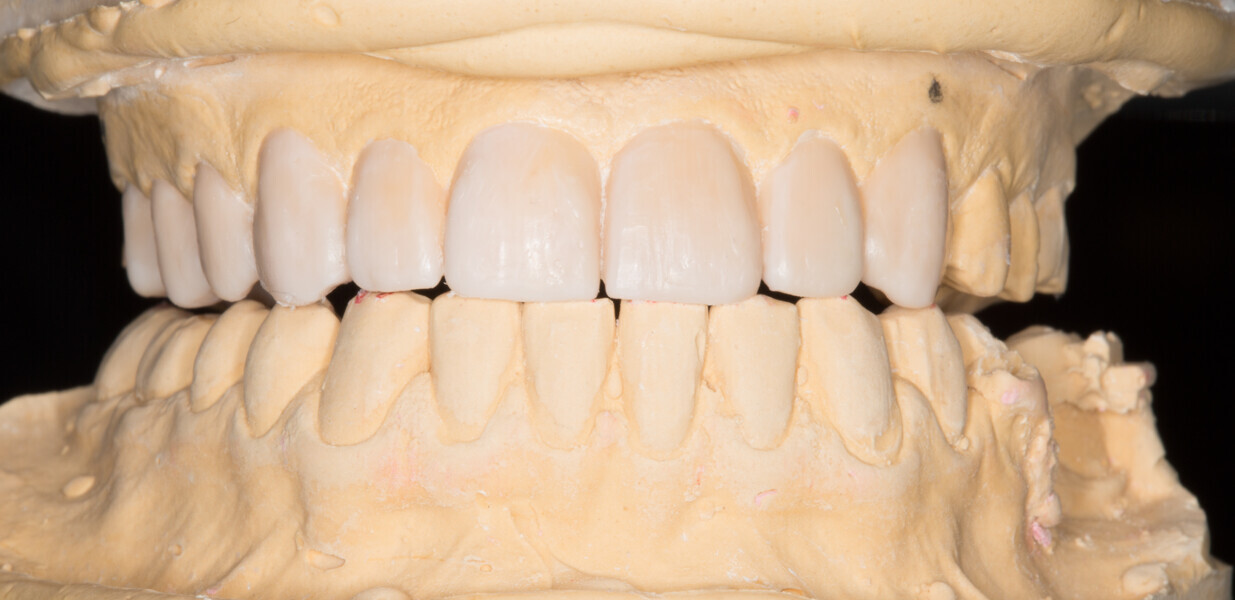

Fig. 16: Final analogue ceramic restorations.

Fig. 17: Final analogue ceramic restorations.

Fig. 18: Final analogue ceramic restorations.

Fig. 19: Final analogue ceramic restorations.